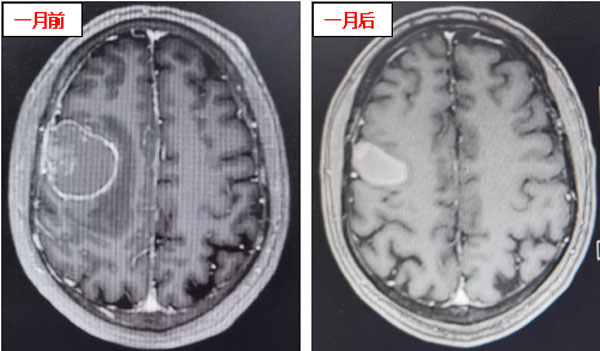

患者在接受3次射波刀治療后,頭痛癥狀明顯減輕,癲癇癥狀消失,肢體肌力明顯好轉。接受治療1后,患者肢體肌力恢復正常,未再出現口角、肢體抽搐及頭痛、頭暈等癥狀,僅左側手指尖偶有麻木感。復查頭顱核磁顯示顱內病灶明顯縮小,周圍無明顯水腫壞死征象,安全性良好,這意味著射波刀治療成功遏制了顱內轉移瘤